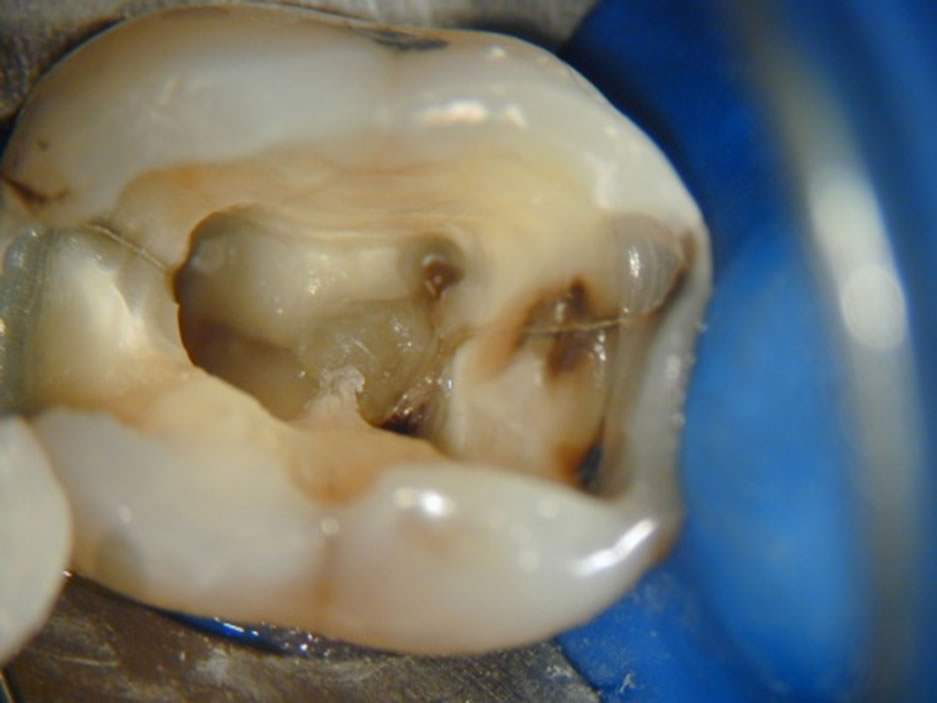

O microscópio operatório para odontologia foi desenvolvido para que pudéssemos ter a visibilidade necessária para detectarmos a entrada dos canais radiculares que recobertos por dentina ou por detritos nos impediam a completa descontaminação dos canais radiculares. Com ele também visualizamos e amplificamos a imagem para detectar possíveis trincas, fraturas ou calcificações que impedem o tratamento. Observem as fotos dos casos clínicos que mostram como conseguimos trabalhar e fotografar os casos com a máquina acoplada ao MO.

Trinca na coroa.